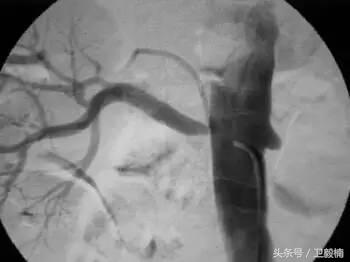

60年*开代**始应用于动脉,使狭窄的血管扩张,70年代研制双腔气囊导管成功后,得到广泛应用,多用于髂、股、腘动脉及肾动脉。肾动脉PTA(或PTPA)多用于肾源性高血压,使狭窄肾动脉扩张,从而降低血压。PTA亦可用于冠状动脉,称为经皮腔内冠状动脉成形术(Percutaneous transluminal coronary angioplasty,PTCA),使硬化的冠状动扩张,以达到治疗冠心病的目的。PTA使用的导管为带胶囊的双腔导管,将胶囊段置于狭窄血管处,囊内注入含有造影剂的液体,加压至3~6个大气压,每次持续10—15o。加压可重复3~4次,多数能使狭窄血管达到扩张的效果。

PTA多用于动脉粥样硬化性狭窄的血管,其机理是粥样斑块受压,内膜和中层撕裂、伸展,使管腔增宽。其他原因的血管狭窄,如多发性大动脉炎,先天性血管狭窄,有时也可用PTA治疗。

(1)PTA +Stent治疗血管狭窄。

(2)溶栓+PTA和(或)Stent治疗血管狭窄。